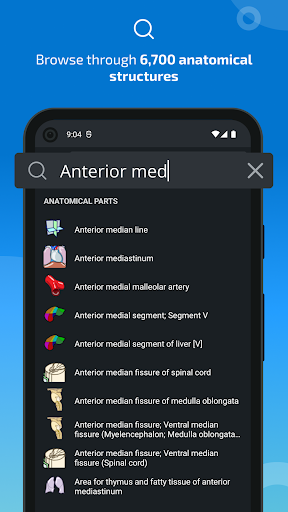

*Find your anatomical parts more easily thanks to the new, more intuitive and powerful search feature